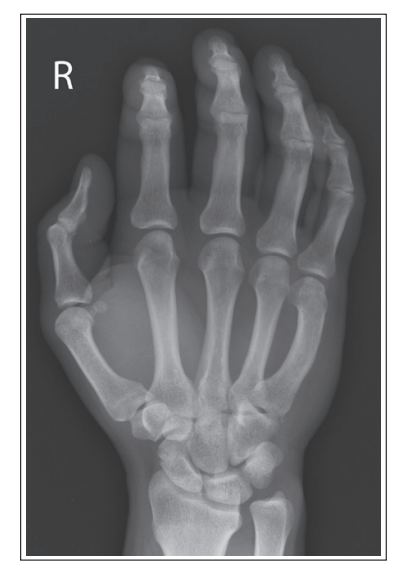

What is wrong with this oblique hand?

The 2nd through 5th MC midshafts are not superimposed, and the 5th MCs anterior to the 3rd through 4th MCs.

External rotation